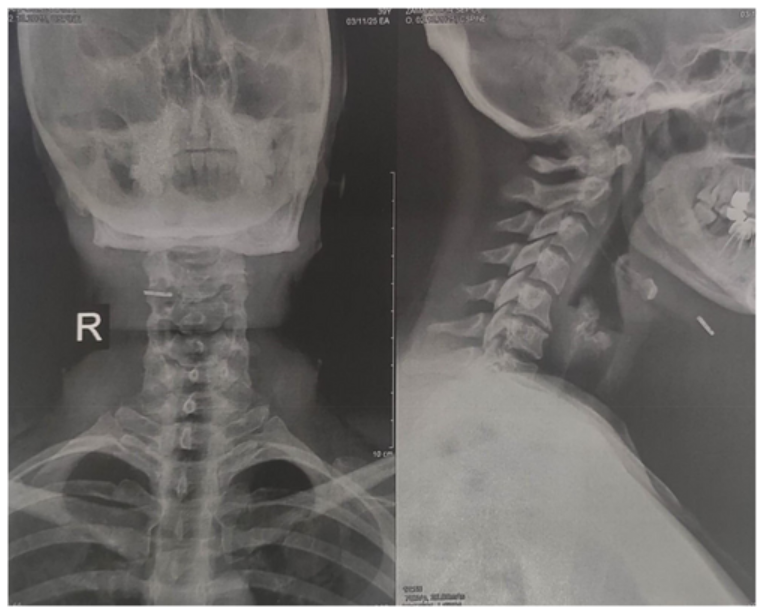

Based on the clinical presentation and procedural history, the differential diagnosis included postoperative fibrosis, fat necrosis, calcified hematoma, granuloma, and retained foreign body related to the prior liposuction procedure. Neck radiography demonstrated an opaque, linear structure located anterior to the hyoid bone on both anteroposterior and lateral views.

Under local anesthesia, clinicians surgically explored the area through a small incision and removed the retained object. The foreign body was identified as a fractured liposuction cannula tip measuring approximately 2 centimeters in length. The patient was prescribed oral cephalexin 500 mg every 8 hours. Weekly follow-up visits were completed for 2 weeks. The researchers reported that the patient recovered uneventfully and that her symptoms resolved completely during follow-up. Written informed consent was obtained.